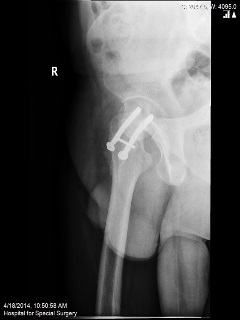

A 37-year-old athletic male underwent an open reduction and internal fixation (ORIF) of his right hip for a stress fracture sustained whilst running the New York Marathon. However, due to non-union of his fracture he underwent revision of the fixation with bone grafting. He presented with persistent pain in the right hip after 18 months from his second operation.

Plain radiographs were performed.

Q. What are your thoughts on the findings of the above radiographs?

The radiographs show non-union of the hip fractures.